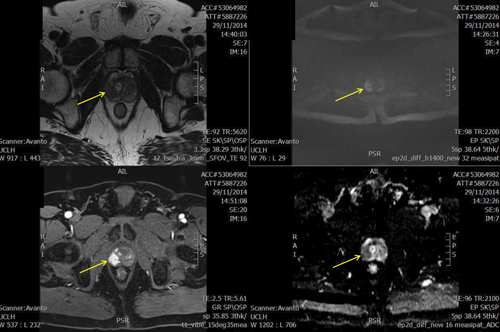

Multiparametric PROMIS MRI showing right peripheral abnormality (arrowed) scoring 5/5. TPM biopsy showed Gl 4+3. Sequences from top left T2, b-1400 diffusion weighted imaging, dynamic contrast enhanced and apparent diffusion coefficient map.